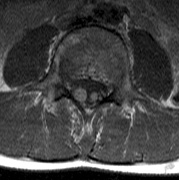

1. Schwannomas most commonly affect the fifth cranial nerve (CN), but any cranial nerve may be affected. In contrast to vestibular schwannomas (CN VIII), these typically do not grow large.84,90 Vestibular schwannomas (acoustic neuromas) are the classic finding in NF2 (Fig. 7). The risk for malignant transformation is low, but may be higher with radiation exposure.84,94

3. Other tumors: low-grade ependymomas and gliomas may affect the cervical spine and Brainstem (Fig. 7).84

Fig. 7. Neurofibromatosis type 2: Images of a 12-year-old boy with deafness and weakness in his arms and legs, whose father has bilateral deafness. Axial T2-weighted (a) and postcontrast axial (b) T2-weighted images reveal bilateral vestibular schwannomas, which are also known as acoustic neuromas (arrows). This is the classic finding of NF2. (b, c) Bilateral schwannomas are seen in Meckel's cave (arrowheads) and a (d) lower left cranial nerve schwannoma extends into the pars nervosa of the jugular foramen (arrow). (e) A part cystic and part solid enhancing ependymoma in seen within the cervical cord and medulla and within the distal cord and conus. (e, f) Thoracic schwannomas are present at numerous levels (arrowheads). Marked enhancement and thickening of the roots within the cauda equina also represent multiple schwannomas.